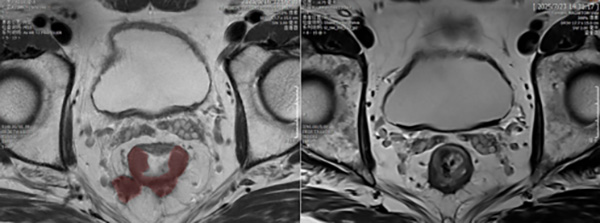

核磁显示放疗后(右)较放疗前(左)肿瘤(红色区域)退缩明显